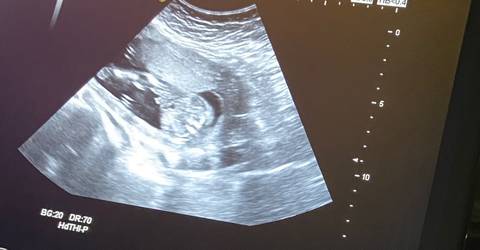

不想了,从此以后好好照顾我的两个宝贝女儿。

你好,从图片上看不出宝宝的性别,不管宝宝是男孩还是女孩,只要宝宝健健康康就好,祝你心想事成

你好。我们是判断不了男宝宝跟女宝宝的,孕期定期检查,我觉得宝宝健康就好的。祝心想事成 。